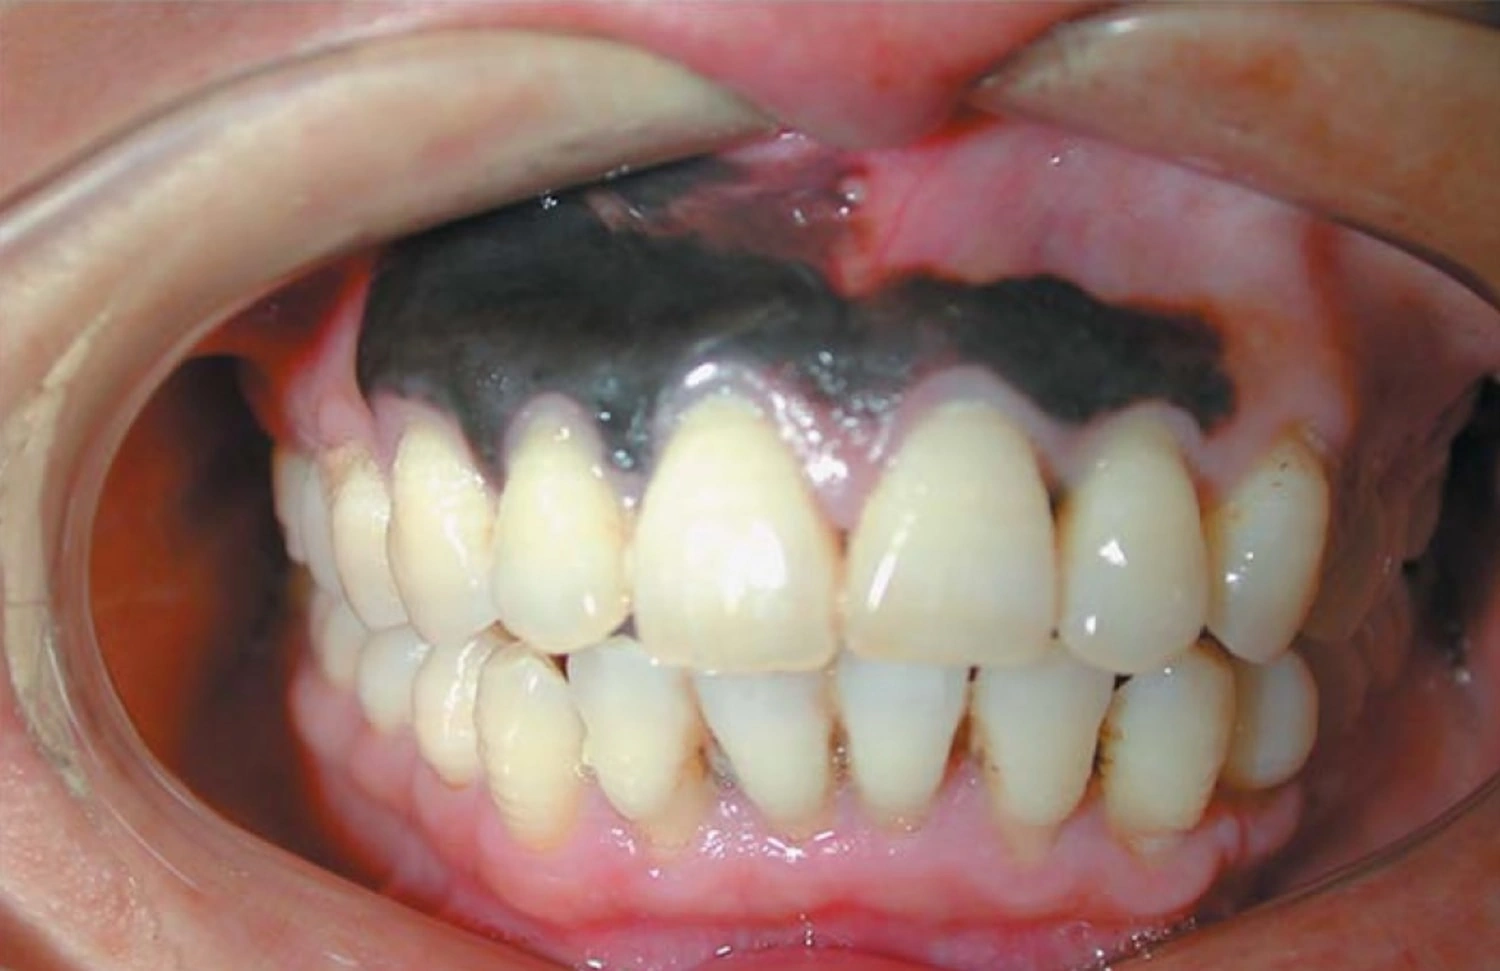

But sometimes… a black spot isn’t so innocent. Oral cancer can show up as a dark (even black) patch, especially if it’s growing, changing shape, or joined by other uninvited guests like sores, bleeding, or swelling in your mouth. That’s where those oral cancer black spot on gums photos come in handy: they show you what real warning signs can look like, including the sneaky, subtle ones you might miss.

So you’re scrolling through oral cancer black spot on gums photos. Some look truly scary—big, irregular dark splotches, raised bumps, or rough-looking patches. Others are… kind of boring. Just a tiny dark dot with nothing special about it. This is the kicker—mouth cancer can show up in lots of ways. Sometimes it’s a bleeding sore, sometimes it’s a sneaky spot that just won’t leave. Want a better picture (pun intended)? Head over to Gum cancer pictures and compare. You’ll find everything from mild oddities to obvious red flags.

According to recent research on oral cancer symptoms by the Mayo Clinic and Healthline, here’s what you might see:

- Black or dark brown spots—sometimes obvious, sometimes just a hint darker than the rest of your gum

- Red or white patches mixed in

- Painless lumps or thick, rough areas

- Unusual lumps on your gums or lips

- Sores that don’t heal for weeks, or never heal at all